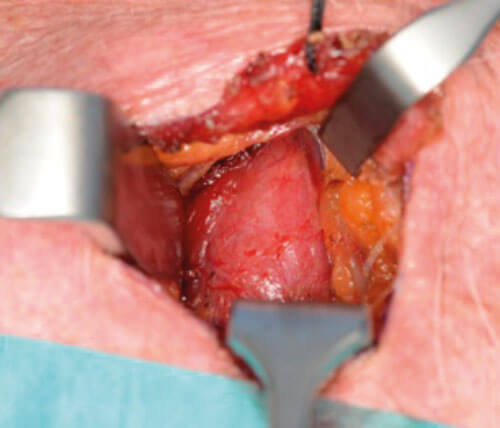

Operative procedure (see Figures 6-11)

Consent for the procedure will take into account risks of surgery including scar, bleeding, infection, damage to recurrent laryngeal nerve (RLN), failure of procedure, and postoperative hypocalcaemia versus the option of not doing surgery and the consequential effects of ongoing hypercalcemia on the body. The patient is positioned with neck extended and a NIM monitor used for RLN monitoring. No local anaesthetic infiltration is used prior to incision. Intraoperative parathyroid hormone levels are not measured routinely as it adds to the cost and duration of the procedure and is usually not required with good preoperative imaging. The preoperative measurements are used intraoperatively. At the start of the procedure, a ruler and marker pen is used to measure the distance from cricoid, and this helps guide incision level on the neck.

Figure 7. Identification of thyroid gland surface.